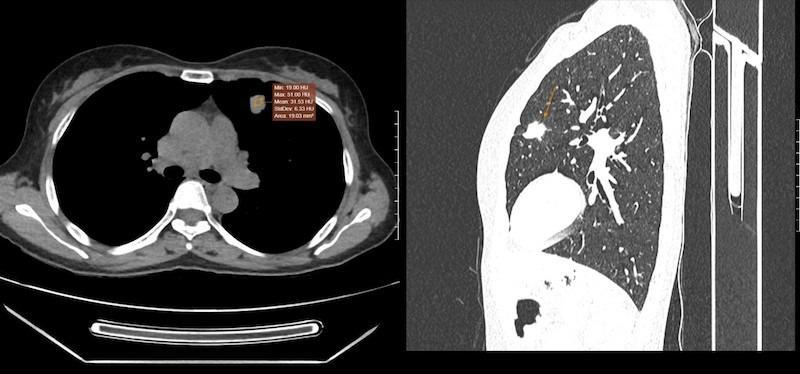

Tuy nhiên, kết quả chụp cắt lớp vi tính (CT) lồng ngực có tiêm thuốc cản quang đã phát hiện một nốt đặc kích thước 21x14mm có bờ tua gai ở thùy trên phổi trái, hình ảnh gợi ý khối u ác tính.

Đồng thời, tuyến thượng thận trái cũng xuất hiện nốt giảm tỷ trọng, nghi ngờ di căn xa. Để làm rõ bản chất khối tổn thương, bệnh nhân được chỉ định sinh thiết xuyên thành ngực dưới hướng dẫn của chụp CT. Mẫu bệnh phẩm sau đó được gửi đến Trung tâm Giải phẫu bệnh MEDLATEC và cho kết quả là ung thư biểu mô tuyến, một thể phổ biến trong ung thư phổi không tế bào nhỏ.